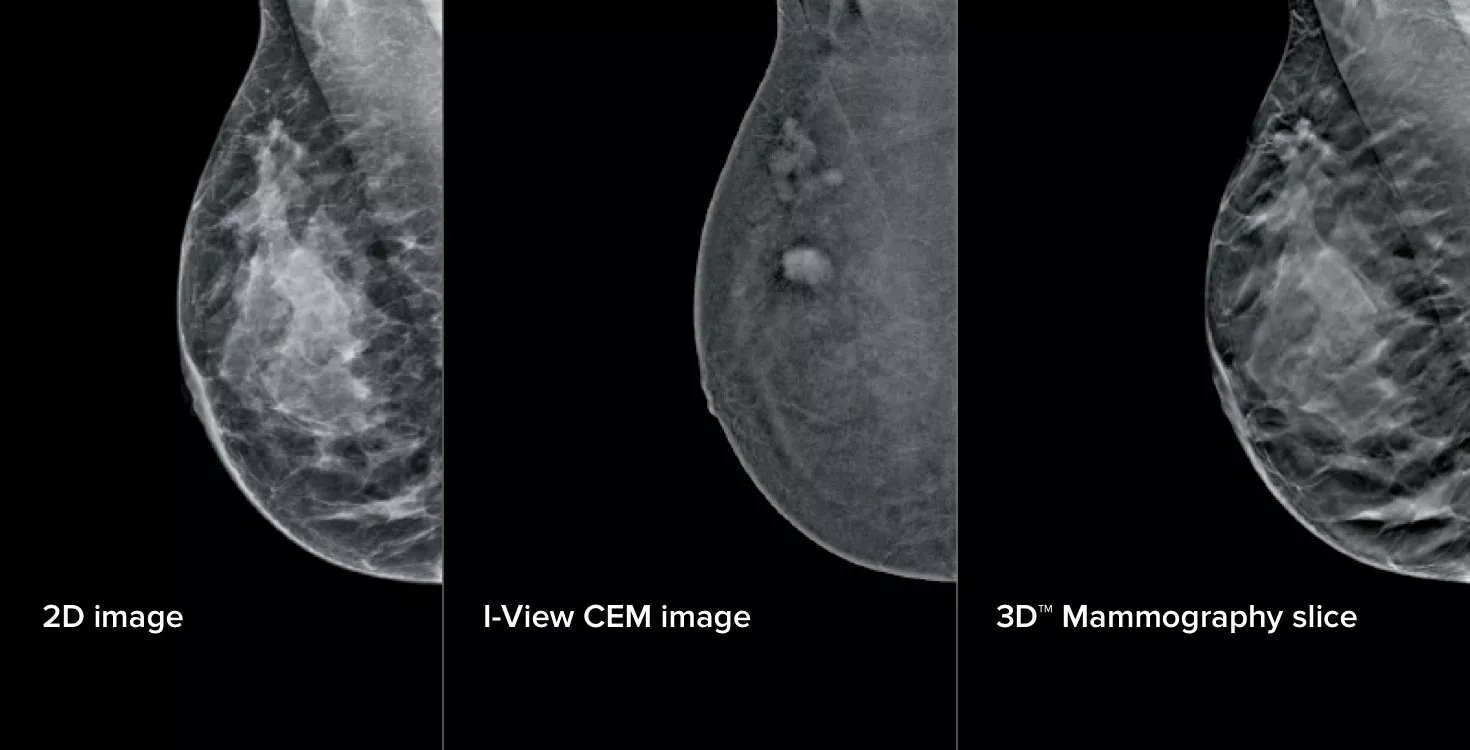

3 Images from 1 Compression

This software captures both anatomical and functional information in a single exam by leveraging our ability to provide 2D, contrast and tomosynthesis images in just one compression.1

I-View CEM imaging is a simple upgrade to any Selenia® Dimensions®* and 3Dimensions™ system, giving breast imaging practices an efficient pathway to expanded diagnostic capabilities.